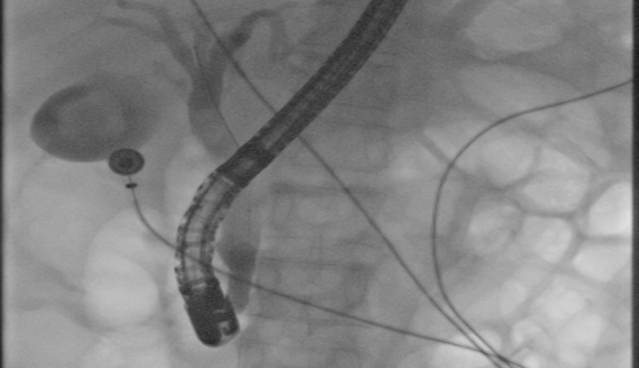

煙台龍軍中醫院有限公司消化内鏡室成立于1996年(nián),擁有奧林巴斯290電子胃鏡、電子結腸鏡、十二指腸鏡、放(fàng)大(dà)胃鏡等最先進的内鏡附件(jiàn),能進行十二指腸鏡逆行胰膽管造影(yǐng)術(shù)(ERCP)、内鏡下粘膜切除術(shù)(EMR)、内鏡粘膜下剝離(lí)術(shù)(ESD)、内鏡下染色判新胃腸道早期腫瘤、巨大(dà)息肉切除、止血、碎石、異物取出、支架植入、贲門(mén)失遲緩症肉毒素注射等先進操作(zuò)技術(shù),多位技術(shù)人(rén)才進修于北京301醫院、上海瑞金醫院、上海東方所膽外科醫院等國(guó)内知名醫院。